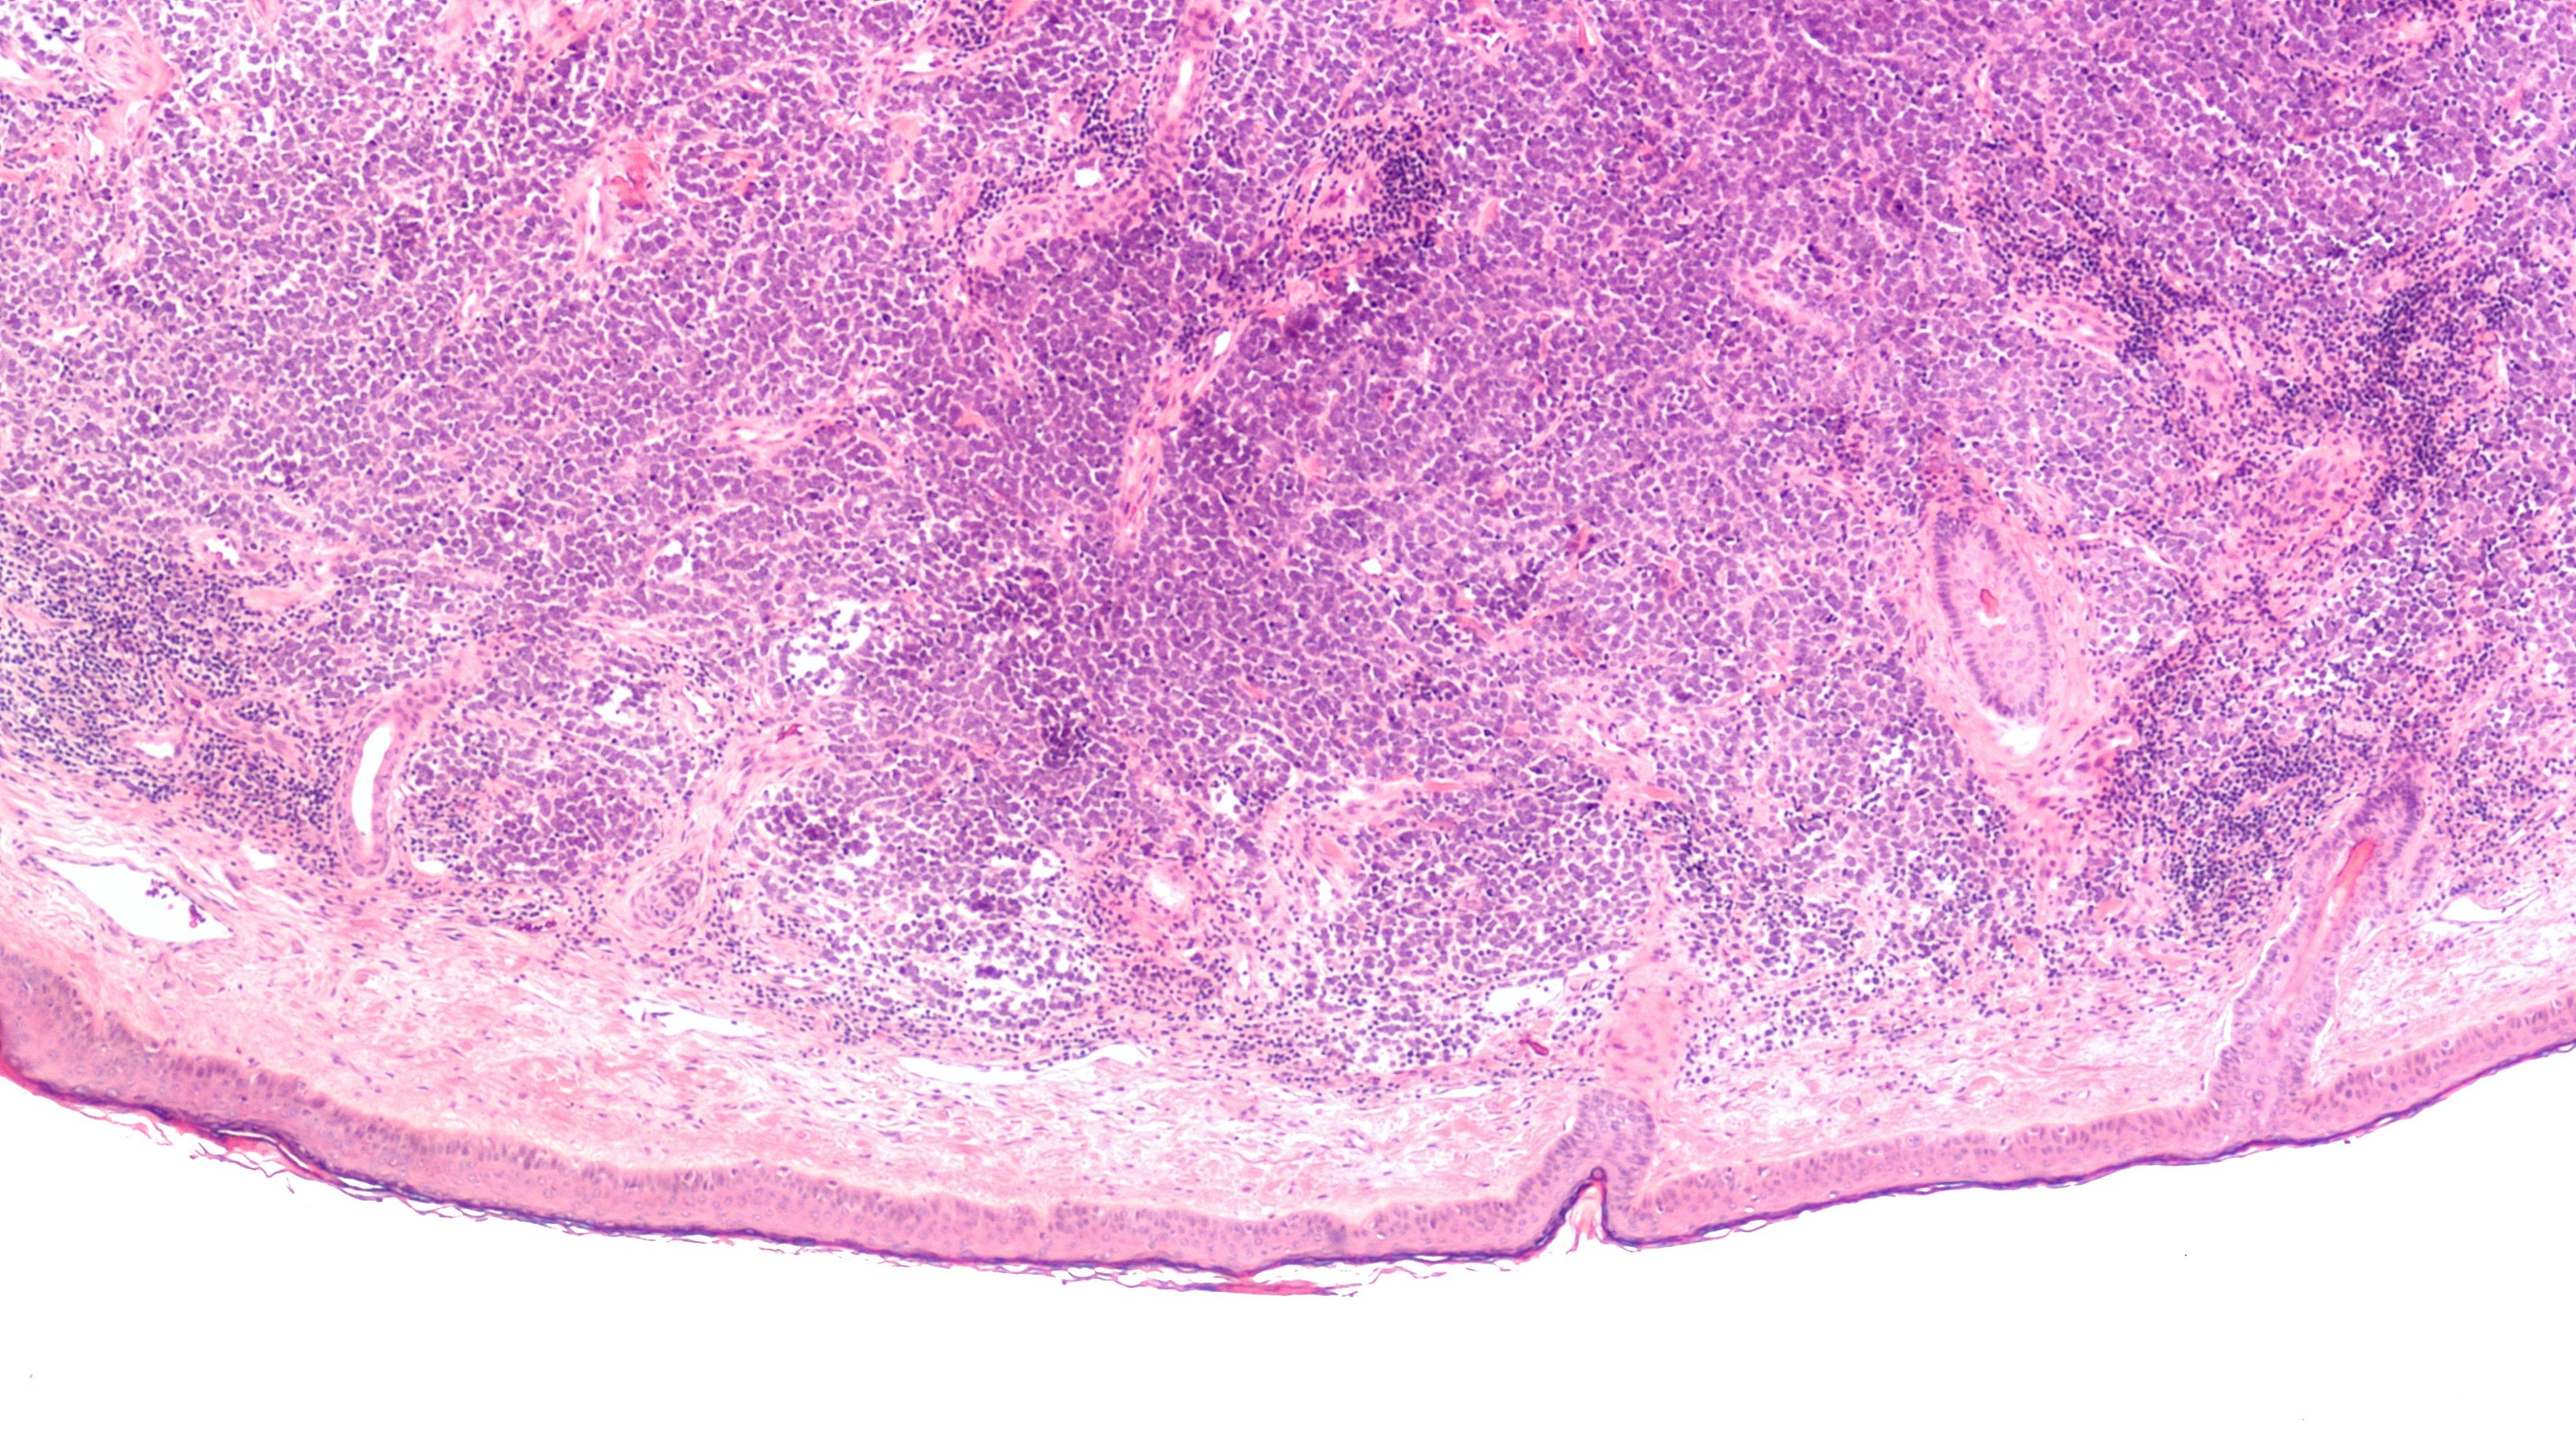

Merkel cell carcinoma is a rare, aggressive cutaneous malignancy that originates due to the uncontrollable proliferation of Merkel cells.

Eccrine porocarcinoma is a rare, aggressive tumor that originates from the intraepidermal ducts of eccrine glands.